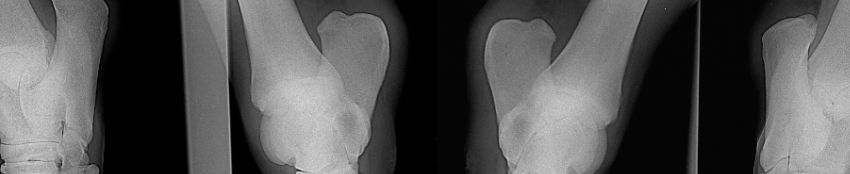

Röntgenaufnahme Gelenk